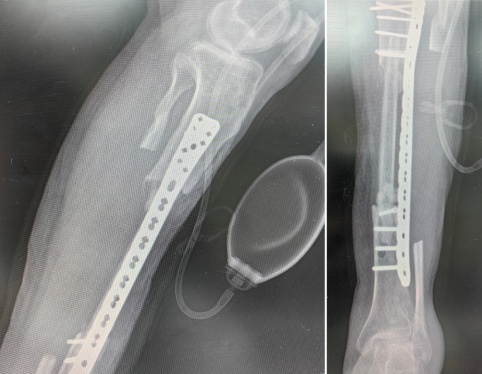

手术按照计划进行,一期切除胫骨感染病灶13cm,并在缺损部位植入抗生素骨水泥旷置。

术前x线表现及切除胫骨感染灶后抗生素骨水泥旷置后的影像学表现

在一期手术后三个月,待感染控制后,采用同侧带血管蒂腓骨移植修复缺损的胫骨。

术后X线表现